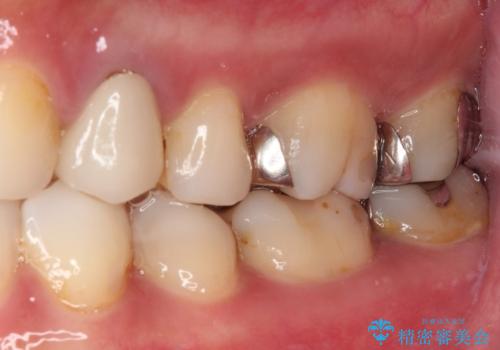

- 奥歯の詰め物や周辺の歯が欠けてしまったとのことで来院された患者様です。

上顎は、元々の詰め物が小さく、欠けた範囲も大きくなかったため、セラミックインレーにて修復治療を行うこととしました。

一方下顎は、元々のむし歯の範囲が広かったため、長期的な予後を踏まえ、セラミッククラウンにて補綴治療を行うこととしました。

特に痛みはありませんでしたが、未然にしっかりとした処置を行うことで、今後むし歯の進行により神経組織が壊死するリスクを低減することが可能となります。